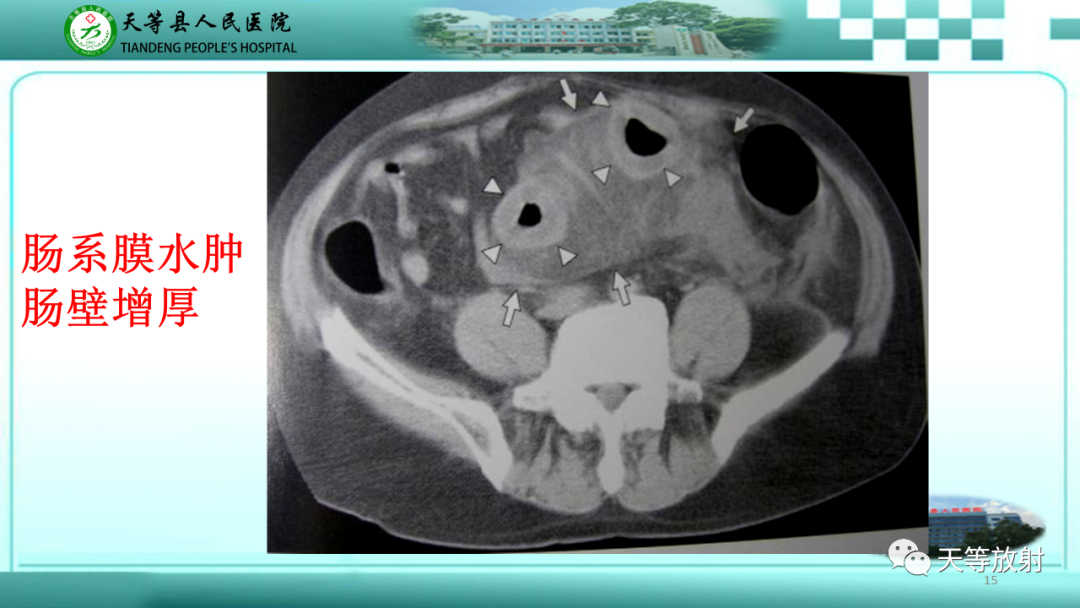

【PPT】缺血性肠病的影像学表现-15